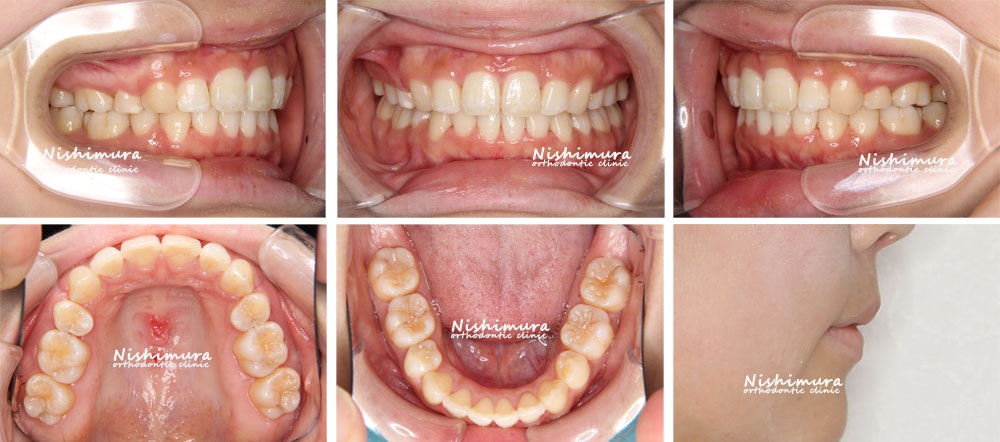

口元が出ている(口ゴボ) 症例4

出っ歯、下顎前歯の凸凹、E-lineを整えたい

叢生、上下顎前突、口唇閉鎖不全

21歳

マルチブラケット装置、歯科矯正用アンカースクリュー

下顎両側第三大臼歯

1年6ヵ月(20回)

治療前

治療前の写真

治療後

治療後の写真